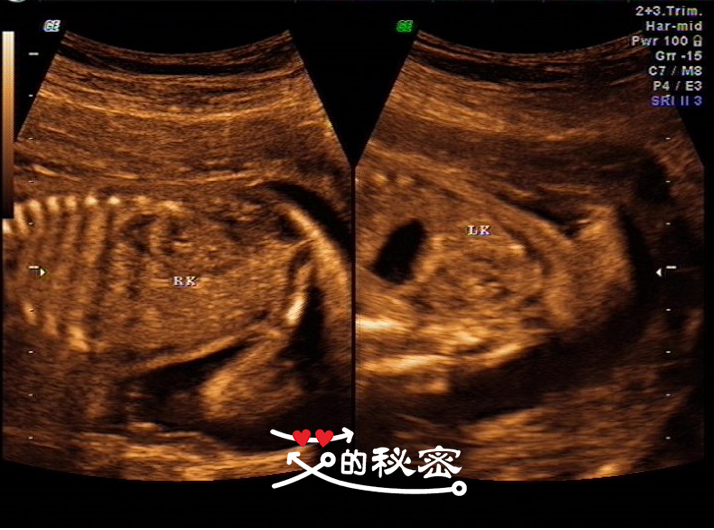

9、胎儿腹部:腹壁未见明显缺损,腹腔未见积液暗区,肺脏可见,胆囊可见,胃泡、双肾、膀胱可显示,双肾内未见分离性或囊性暗区。英文的意思:STO胃,GB胆囊,AC腹围,RK右侧肾脏,LK左侧肾脏。